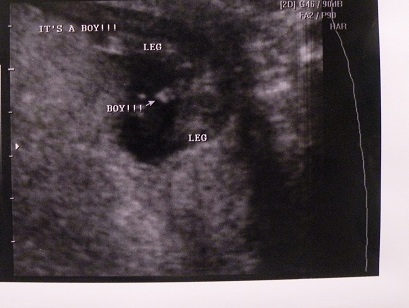

I just had an u/s done when I was 15w2d, where the tech told us we were having a boy. I was truly shocked bc according to Ramzi method baby came up girl (implanted on left side), the HB has always been high (at 8 wks was 150something, 12 wks it was 171, & is now 158-160), other OWT's/tests came out girl, plus my gut feeling said girl & I've not been wrong in all my pregnancies. Here are the potty shot pics, ANY possible way this could end up a girl?

Attachment 5960